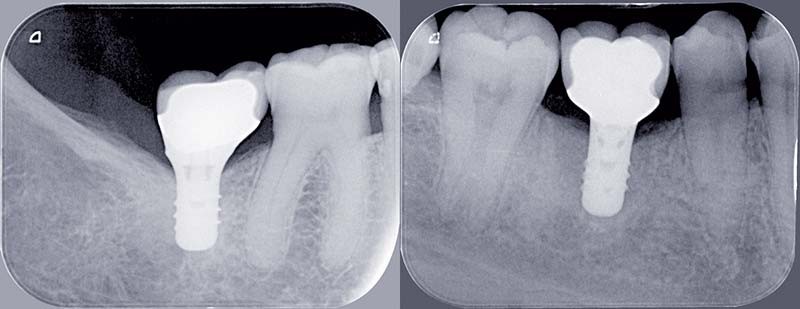

Le traitement d’un édentement unitaire postérieur peut se réaliser par la mise en place d’une fixture implantaire et la réalisation d’une prothèse unitaire. Afin de favoriser l’intégration et la pérennité de cette structure prothétique, certains facteurs sont à évaluer. Différentes options thérapeutiques quant au choix des matériaux prothétiques ou des techniques sont évaluées pour essayer de déterminer dans le traitement les facteurs pouvant au niveau de la prothèse réduire les échecs et donc conduire au succès d’un traitement à long terme.

L’analyse clinique initiale dans le cas d’un édentement unitaire postérieur doit guider la mise en place de l’implant pour permettre, chaque fois que cela est possible, la réalisation d’une prothèse transvissée.